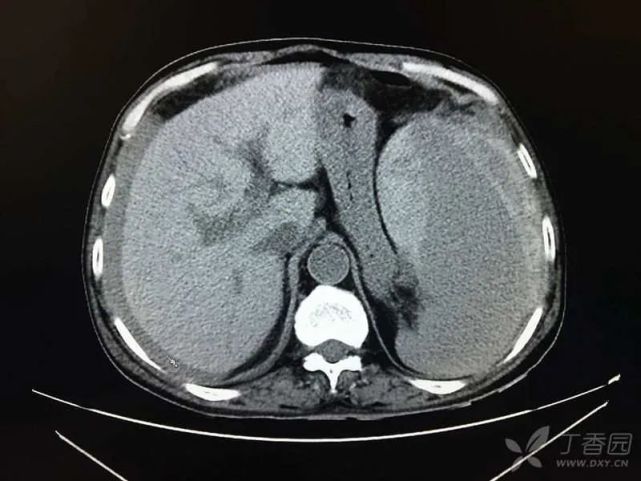

病毒全套、EBDNA、CMVDNA、ANCA、自身免疫系列、自身免疫性肝病谱、甲状腺功能均无明显异常,K-F 环阴性。MRCP:胆囊结石伴胆囊炎表现,胆总管轻度扩张,壁稍强化(炎性改变?),脾切除术后改变,肝脏再生结节形成可能性大,双肾多发小囊肿征,少量腹水(图 2)。

图片

(图 2 MRCP 检查结果)